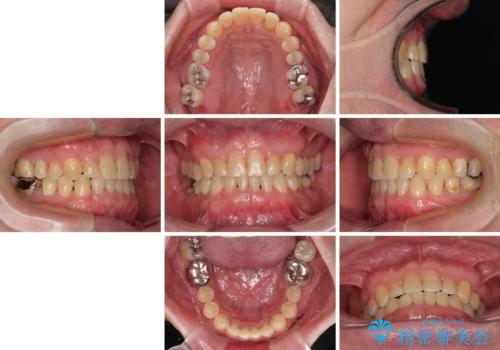

- 上下前歯の反対咬合と左下奥歯の痛みを気にして来院された患者様です。

歯並びや口元の印象、奥歯の咬み合わせから、非抜歯にて矯正治療を行うこととしました。

インプラント埋入による仮歯の装着や、前歯の反対咬合の改善は比較的スムーズに達成されましたが、舌突出癖などの影響による、歯列全体のスペースを閉じることが難航し、期間がかかってしまいました。

治療後も舌突出癖が残っていると、あっという間にスペースができてしまうので、トレーニングを継続するように指導をしています。